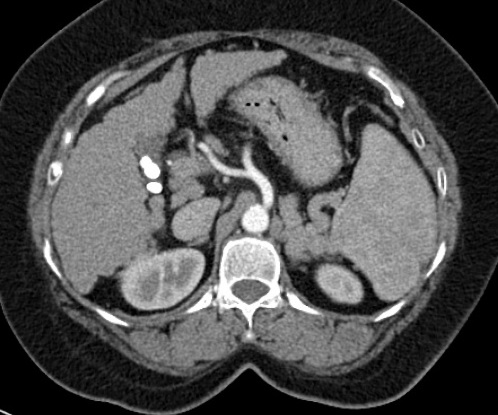

Image radiologique TDM en coupe

axial du splenomegalie d'une cirrhose du foie . La

rate est volumineuse ,a isodense , sa diametre

anterieuse - posterieuse depasse 11cm ,systeme veine

splenique est distendue . Le foie droit est a bord

crenele , reduction de volume , systeme veine porte

est distendue et en presence de l'ascite peritoneale |